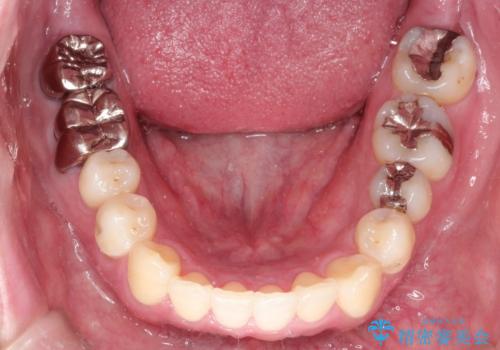

全体的ながたつきをインビザラインで改善

- 全体的ながたつきを主訴に来院されました。

歯と歯の間をわずかに削って、スペースをつくり並べる計画としました。

しっかりと、マウスピースの装着時間を守っていただいたので、スムーズに治療をおえることができました。